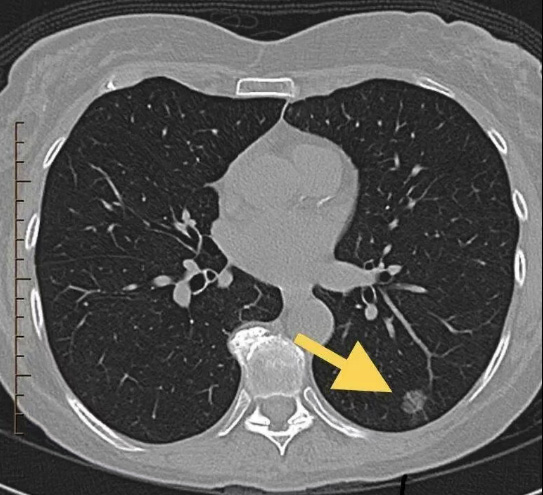

肺結(jié)節(jié)通常指直徑小于3厘米的局灶性、類圓形、密度增高的實(shí)性或亞實(shí)性肺部病變,這些病變在影像上不伴有肺不張、肺門淋巴結(jié)腫大或胸腔積液等征象。

采用低劑量薄層CT掃描(LDCT)